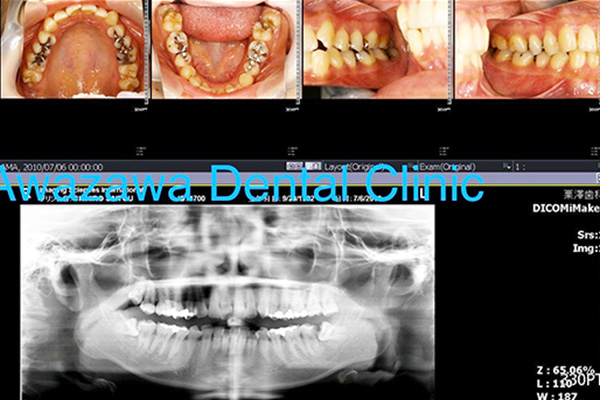

歯周病とは 歯の表面につくプラークにより、歯肉や歯槽骨などの歯を支える組織が破壊されて放っておくと歯が揺れだして最終的には抜けてしまう(抜かなくてはならなくなってしまう)恐ろしい病気です。

重症になるまでは痛みなどの自覚症状がないまま何年もかけてゆっくりと進み、症状が出た時には相当進行している場合が多く、日本人の成人の80%以上の方々が罹患していると言われています。

歯周病治療の最も重要な事は病気の早期発見ならびに早期の予防処置です。

歯周病で失ってしまった骨は基本的には元へは戻りません(部分的に再生する事は可能ですが全体的に失ってしまった骨は残念ながら元に戻す事はできません)。ちょうど年齢が若返る事ができないのと似ています。